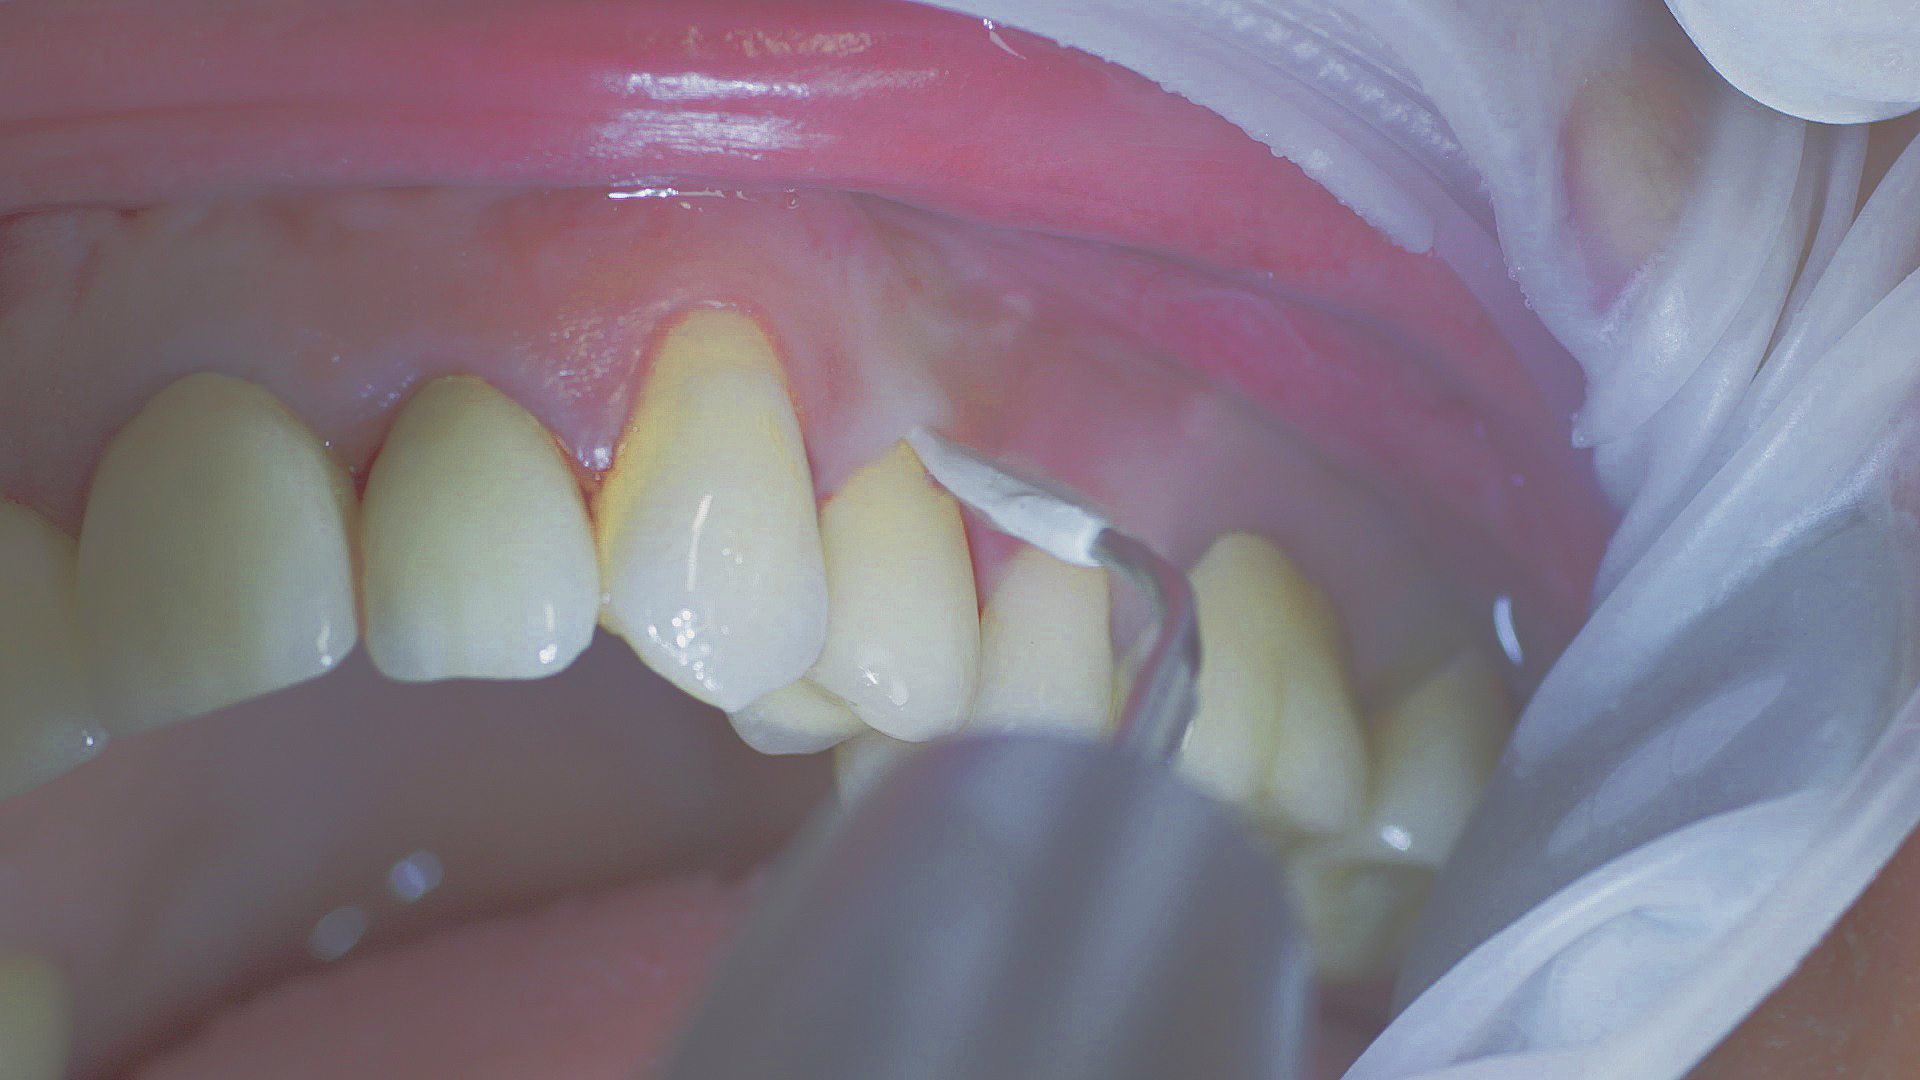

Si nécessaire, un traitement parodontal préventif est effectué. Un nettoyage dentaire professionnel contribue dans un premier temps à des conditions gingivales saines. Il permet d’éliminer le tartre (Fig. 1) et le biofilm (Fig. 2) jusque dans le sulcus gingival. En association à des consignes d’hygiène buccodentaire méticuleuses,

il élimine également à long terme le risque de récidives d'inflammation chez le patient.[15]

Dans le cadre du traitement parodontal préventif, le détartrage subgingival (debridement en anglais) est effectué à l'aide d'appareils à ultrasons et d'inserts paro spécifiques (Fig. 3). Des instruments manuels peuvent également être utilisés. En fonction de la situation, d'autres mesures, y compris chirurgicales et régénératives, peuvent s’avérer nécessaires.